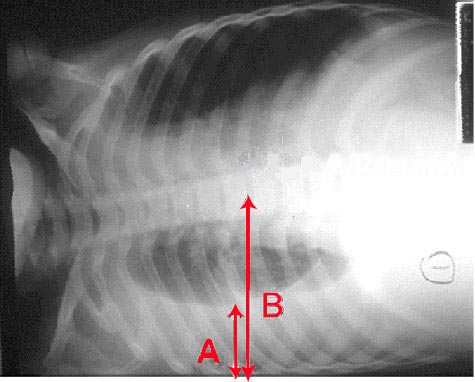

English: Pleural effusion Chest x-ray of a pleural effusion. The arrow A shows fluid layering in the right pleural cavity. The B arrow shows the normal width of the lung in the cavity